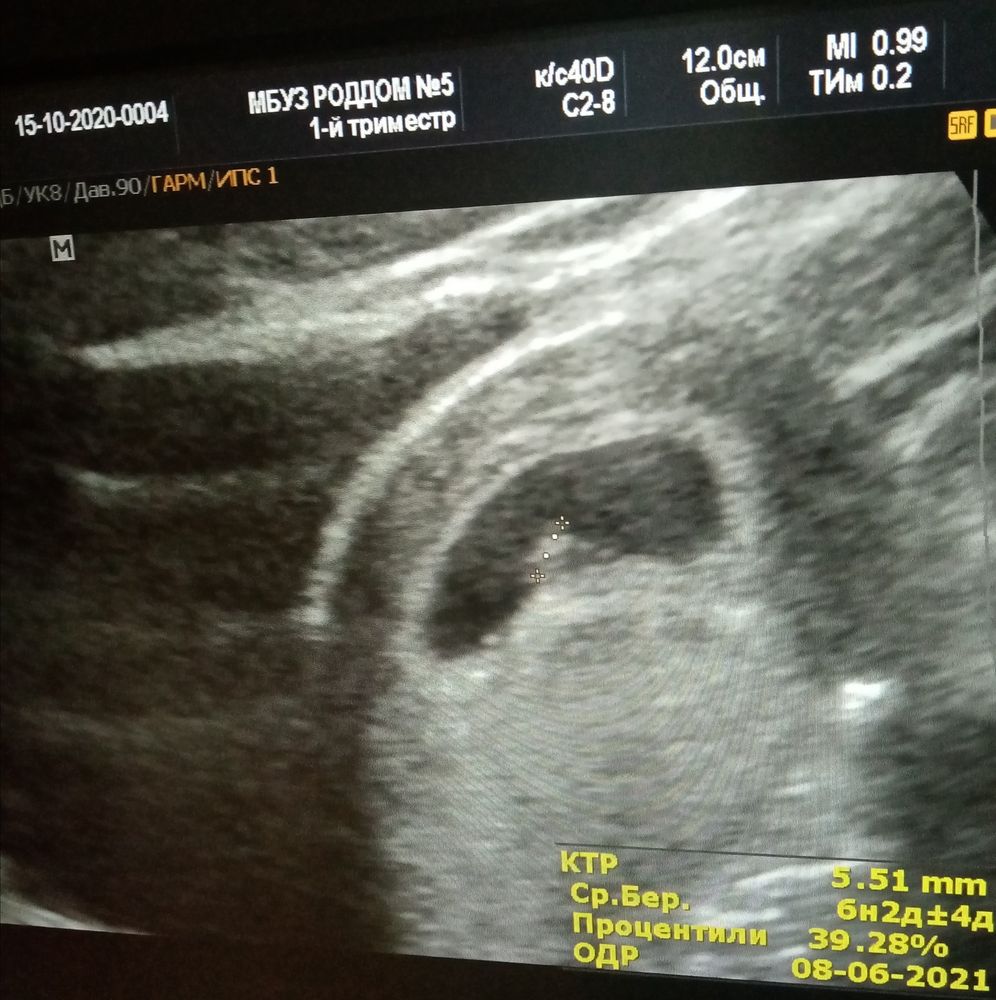

Наше первое УЗИ)

Девочки, совершилось, я была на УЗИ, беременность подтвердилась, поставили около 6,4 недель, 167 ударов в минуту наше сердечко, и вот что, я скажу, если долго ждете не спите ночами и плачите, НЕ НАДО, я перестала плакать и думать о том как сильно хочу маленького и вот положительная полосочка, поэтому девочки, не отчаивайтесь и все у вас получится.

Поздравляю! Я тоже вчера первый раз была на УЗИ, мы с Вами рядом, у нас 7+1 и КТР 9 мм

Алеся, у нас уже 6,4 неделек беременности, какая неделя задержки не скажу, уже не помню) но тест делала на 3х днях задержки, были вот такие тесты) и узи сдела примерно 2 недели было задержки